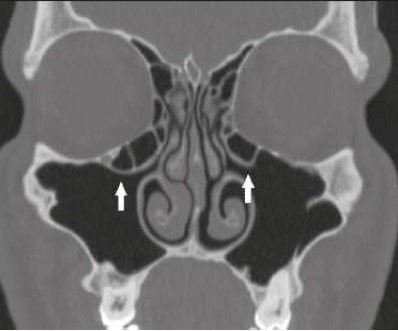

O avanço nos exames de imagem permitiu uma ampliação do conhecimento anatômico e melhor planejamento para tratamento dos pacientes. A introdução da cirurgia endoscópica nasossinusal funcional na década de 1980 trouxe uma mudança drástica na abordagem dos pacientes com rinossinusite recorrente ou refratária, aliviando os sintomas e melhorando a qualidade de vida. A imagem mostra um corte coronal de uma tomografia computadorizada, sendo possível observar na ponta das setas: